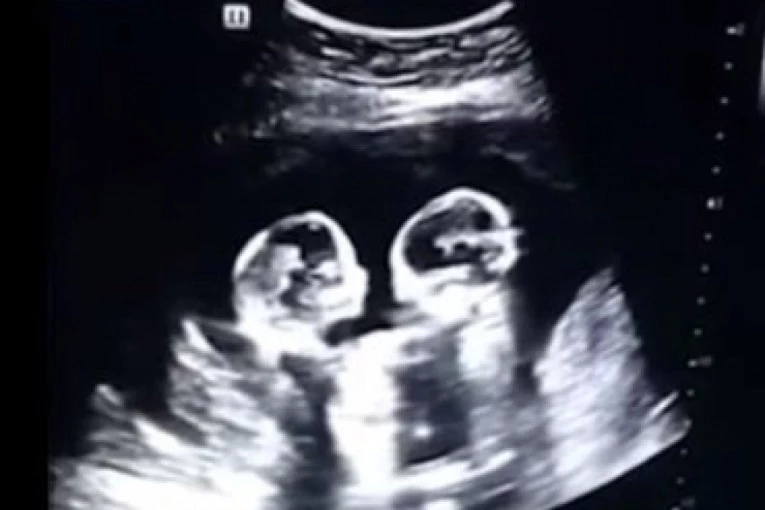

Dve još nerođene devojčice već su postale zvezde interneta. Naime na snimku ultrazvuka jedne Kineskinje koja nosi bliznakinje, vide se dve devojčice koje kao da jedna drugu udaraju i šutiraju.

Snimak od prošle godine je na društvenim mrežama podelio njihov otac Tao (28) koji kaže da je njegova žena tada bila u četvrtom mesecu trudnoće. Ipak, on je rekao da nije očekivao da će njegova deca postati internet zvezde još pre rođenja.

Kako je rekao, na kasnijem snimku, nastalom u januaru, devojčice su snimljene zagrljene, pa izgleda da su se izmirile.